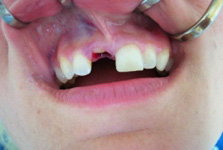

Klasickým příkladem a indikací pro použití implantátu je ztráta jednoho zubu (v tomto případě v předním – frontálním úseku) v jinak zdravém, nepoškozeném chrupu.

Nejčastější příčinou takové ztráty je sportovní nebo dopravní úraz.

Náhrada jednoho zubu pomocí implantátu je možná také v postranním úseku chrupu. Při ztrátě většího počtu zubů ve frontálním nebo postranním úseku může být mezer uzavřena větším počtem jednotlivých implantátů.

Při ošetření pomocí jednotlivých implantátů zůstávají sousední zuby neporušené – intaktní. Při klasickém ošetření pomocí můstků musejí být tyto zuby obroušeny!